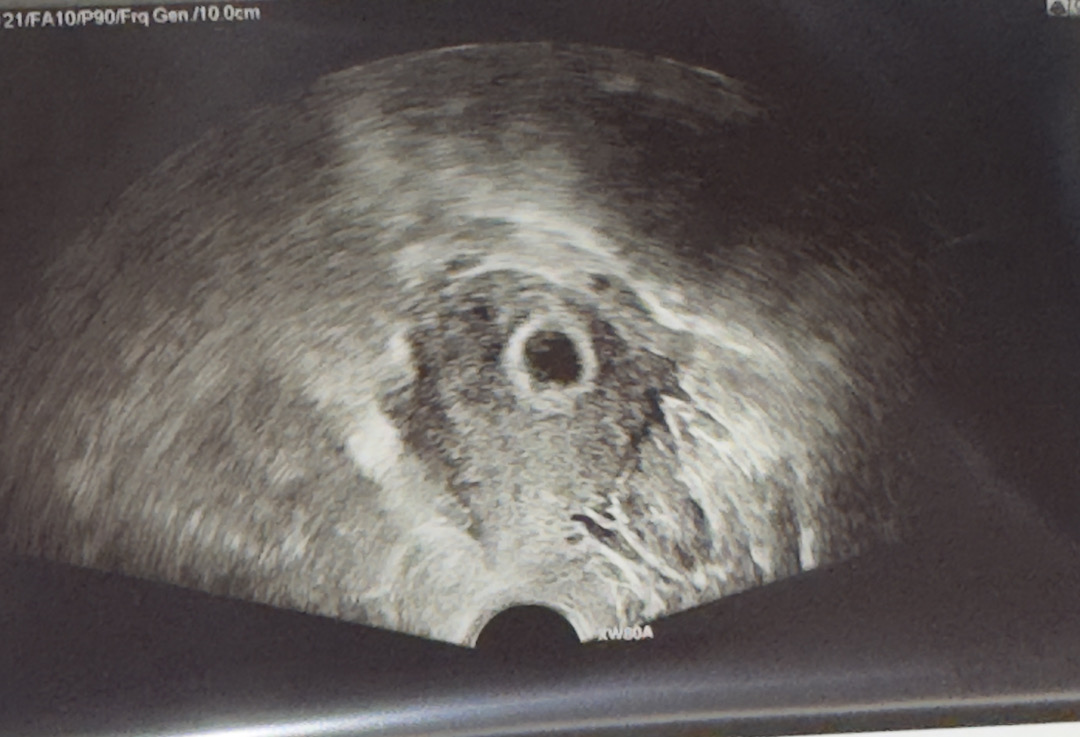

6주1일차 초음파 사진 봐주세요ㅠ

아기집은 잘 크고있는데 난황이 잘 안보이네요ㅠ 사진속에 흐리게 동그라미가 있긴해요. 6주초기 초음파 다들 어떠셨나요?